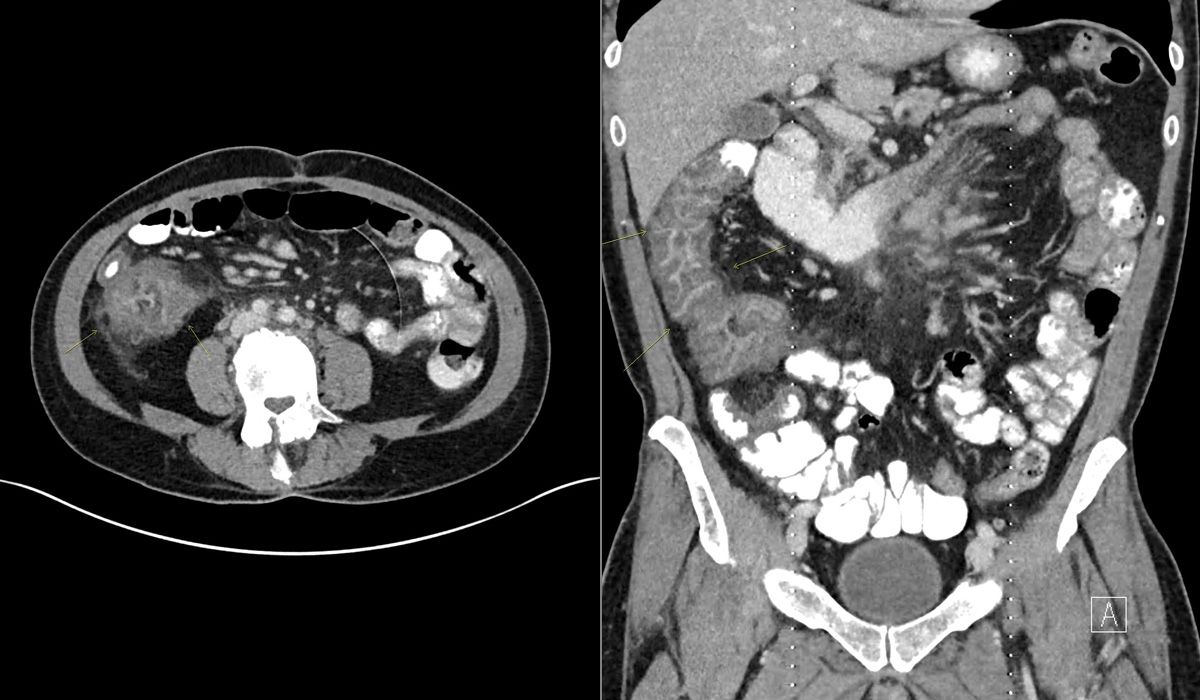

A 30-year-old man who recently underwent induction chemotherapy for bone marrow transplant is admitted with neutropenia and right lower-quadrant abdominal pain. Coronal and axial images from a contrast-enhanced CT scan of the abdomen and pelvis are seen below (white dots and partial circle on images are artifacts).

What is your diagnosis?